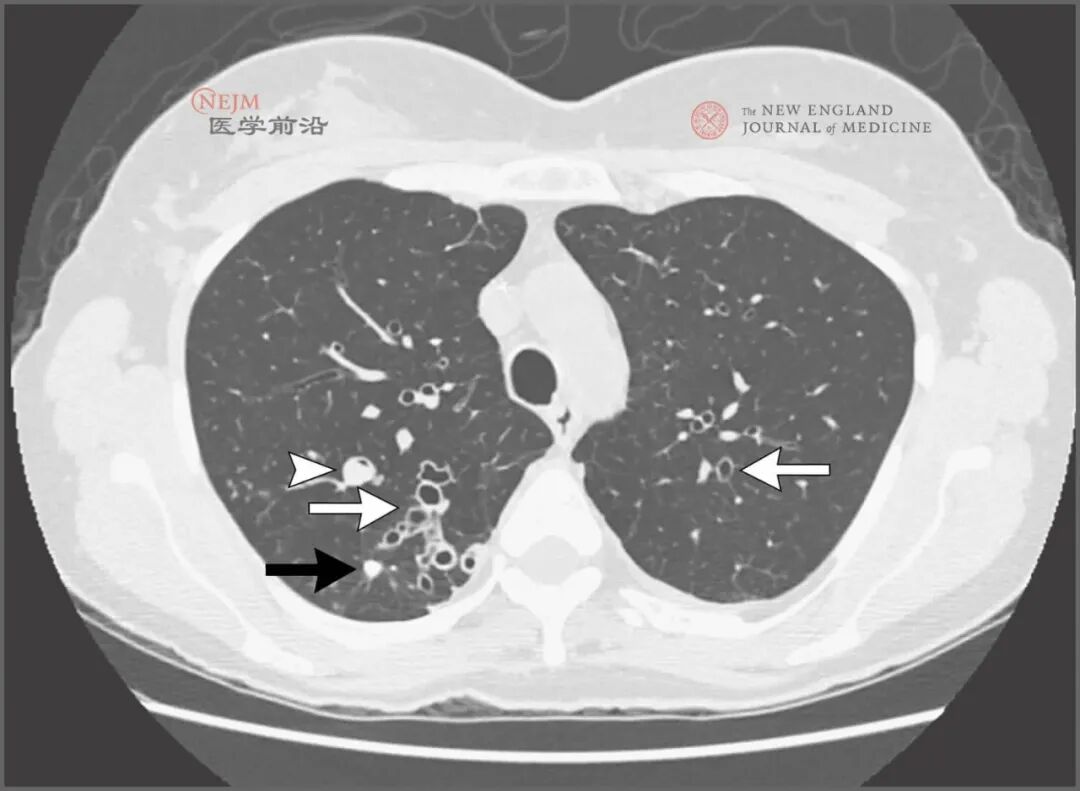

胸部X线片显示“轨道征”,累及双肺上部和左肺下部,这一发现符合支气管扩张。肺容量正常。无实变影,无肺水肿、胸腔积液或者纵隔或肺门淋巴结肿大的证据(图1)。

胸部后前位X线片显示“轨道征”,累及双肺上部和左肺下部(箭形),这一发现符合支气管扩张。未见其他异常。